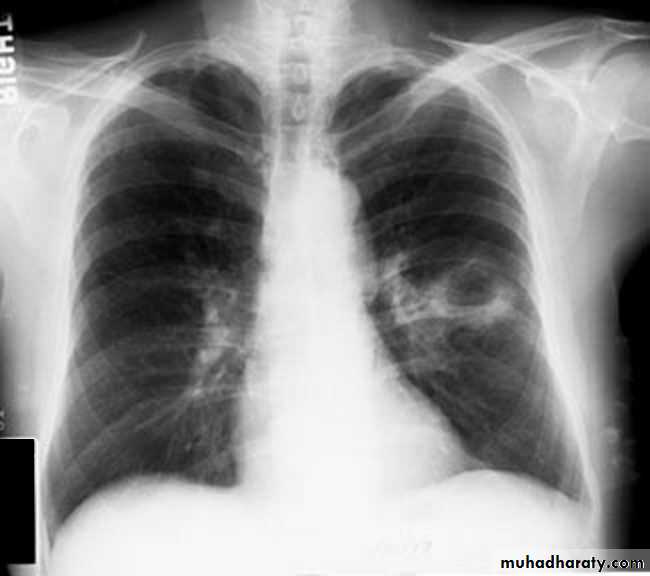

Hodgkin Lymphoma. A. Posteroanterior chest radiograph in a 35-year-old man shows a large, lobulated mediastinal mass. B. Contrast-enhanced CT at the level of the aortic arch shows bulky anterior and middle mediastinal lymphadenopathy